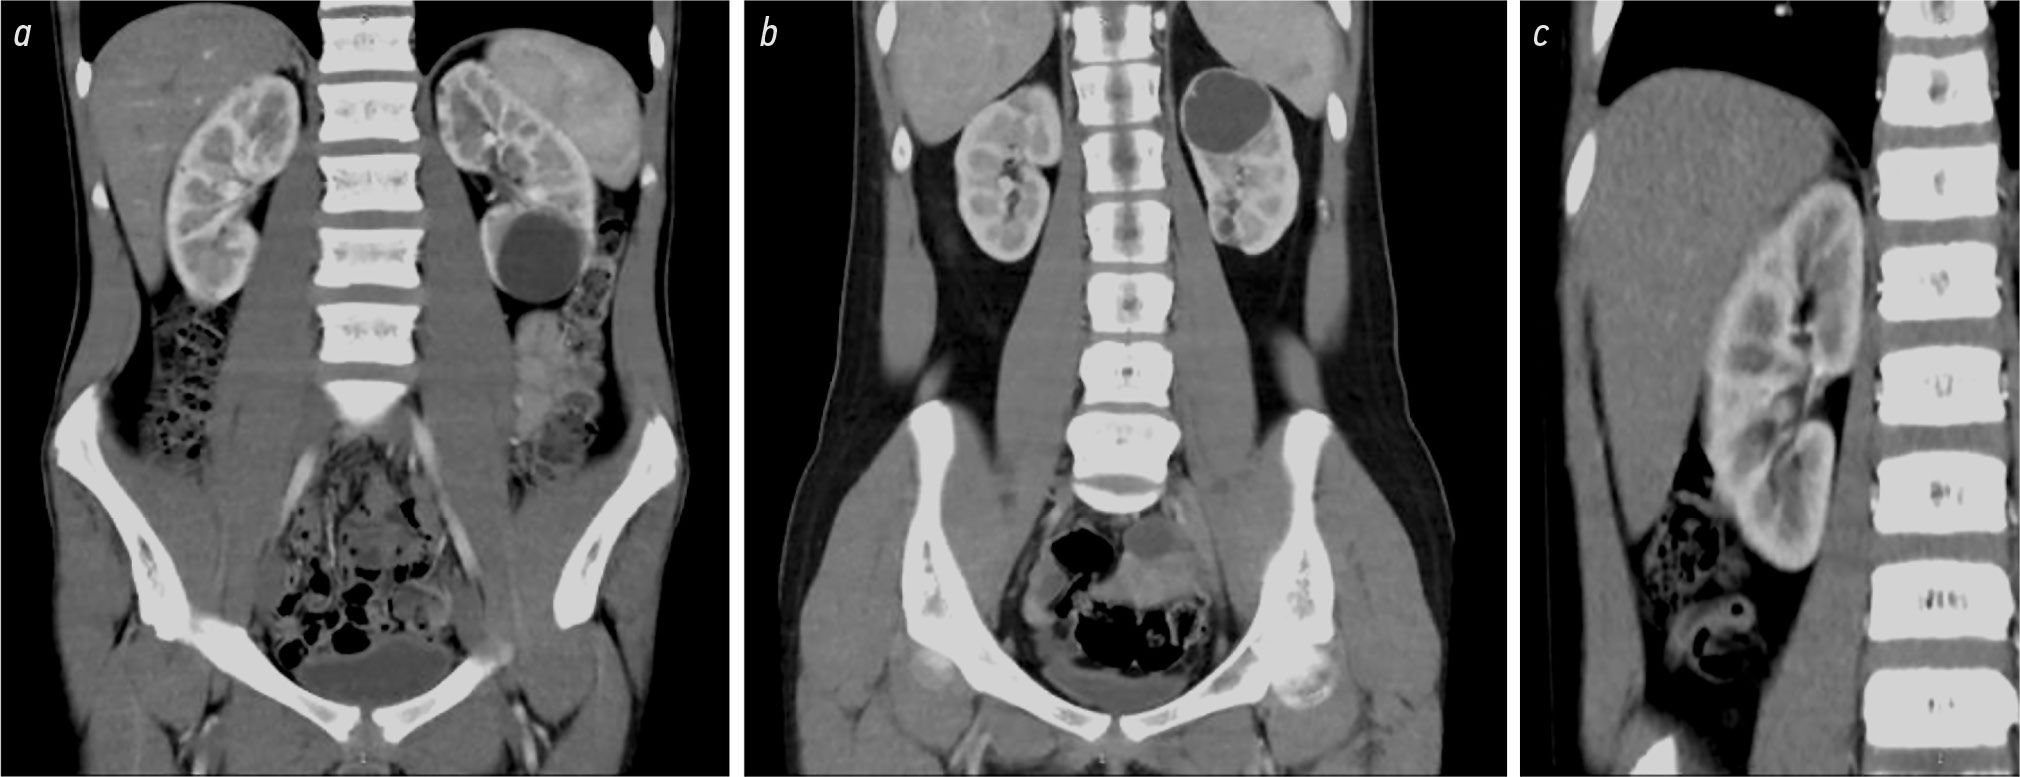

Периоперативные данные пациентов были ретроспективно собраны из историй болезни. Диагноз ПКП был установлен с помощью УЗИ почек, а также данных мультиспиральной компьютерной томографии почек с внутривенным введением контрастного вещества (рис. 1). После получения результатов компьютерной томографии (КТ) все кисты были классифицированы как ПКП II стадии. Показания к операции устанавливались на основании результатов динамического наблюдения и данных УЗИ. При появлении признаков роста ПКП или клинического ухудшения (развитие болевого синдрома, связанного с увеличением кисты), родителям пациентов предлагали операцию. Родители пациентов были информированы о предстоящей операции и дали согласие на проведение процедуры робот-ассистированной декортикации наружной части ПКП и аргон-плазменной коагуляции внутренней выстилки кисты. Технический успех операции определялся как достижение иссечения оболочек кисты почки по границе аваскулярной зоны с возможностью аргон-плазменной коагуляции внутренней выстилки внутрипочечного остатка кисты. Ниже приводится описание деталей операции.

Рис. 1. Компьютерные томограммы пациентов с кистами нижнего и верхнего полюса левой почки: a — пациент № 1, киста нижнего полюса левой почки; b — пациент № 2, киста верхнего полюса левой почки, c — пациент № 3, киста верхнего полюса левой почки.

Fig. 1. Computer tomograms of patients with cysts of the lower and upper poles of the left kidney: a — patient No. 1, cyst of the lower pole of the left kidney; b — patient No. 2, cyst of the upper pole of the left kidney, c — patient No. 3, cyst of the upper pole of the left kidney.